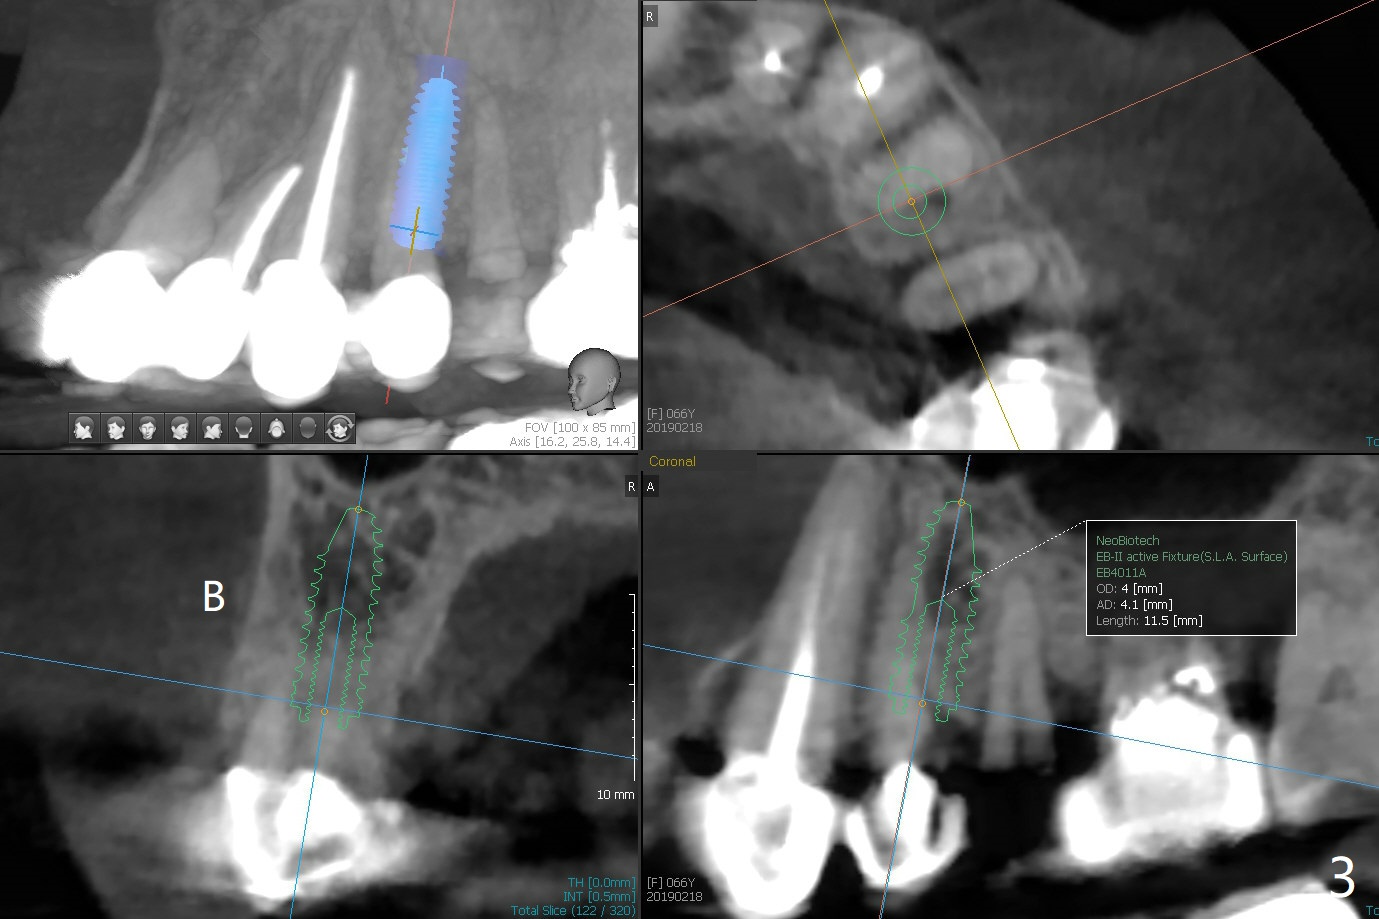

68岁女右上4个植牙后(图一),左上4(12号牙)根尖周围炎,根管闭锁(图二),牙周袋9毫米。切割3,4连冠,拔除4,为了减少腭侧骨板吸收,植体也不要植入太腭侧(图三,四)。其实顺腭侧根钻洞偏近中,很难纠正,最后位点保存